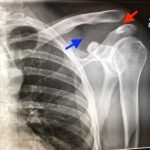

Plain films of the left shoulder showed elevation of the left clavicle above the acromion. There was an increase in the acromioclavicular (AC) and coracoclavicular (CC) distances (increased joint distances marked with red and blue arrows, respectively). A normal AC joint measures 1-3 mm whereas a normal CC distance measures 11-13 mm.1 The injury was classified as a Rockwood type III AC joint separation.